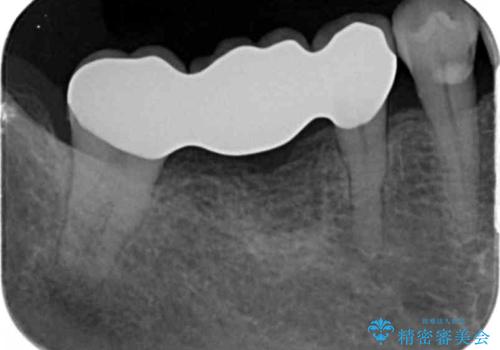

- 41.8万円(仮歯・ジルコニアクラウン×3・小矯正)費用は治療当時の料金となります

ブリッジが長く機能できるように噛み合わせの微細な調整は非常に大切ですが、支台となる歯の神経を温存できるかどうかも非常に大きな要因です。

今回の治療ではブリッジ製作に先んじて小矯正を行うことで、より予知性を高める治療をおこなうことができました。